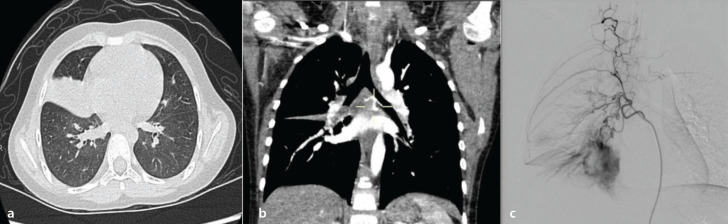

Results: Of the 74 children with pulmonary hemorrhage in this study, seven exhibited signs of consolidation in the middle lobe of the right lung, and bronchial-pulmonary shunt existed in all of them. A total of 30 children with BA-pulmonary artery shunt (PAS) had BA tortuosity and thickening. Regarding primary BA-PAS, the middle lobe and lower lobe of the right lung were involved in 94.1% (16) of the children. Those with a fistula located in the middle lobe of the right lung accounted for 58.8% (10 cases), of which 40.0% (four cases) presented consolidation. In this study, 41.2% (seven) of the children with primary BA-PAS exhibited no abnormal changes on chest CT, and 58.8% (10 cases) exhibited abnormal changes in the unilateral lung.

Conclusion: For children with pulmonary hemorrhage who have consolidation in the right middle lobe, the formation of BA-PAS should be anticipated. The possibility of primary BA-PAS should not be disregarded in children with pulmonary hemorrhage with tortuosity and dilation of BAs, despite no apparent abnormalities on lung CT, or ground-glass density or consolidation on only one side.

Clinical significance: The chest CT of patients with pulmonary hemorrhage showed consolidation of the right middle lobe of the lung, which was highly likely to indicate BA-PAS.